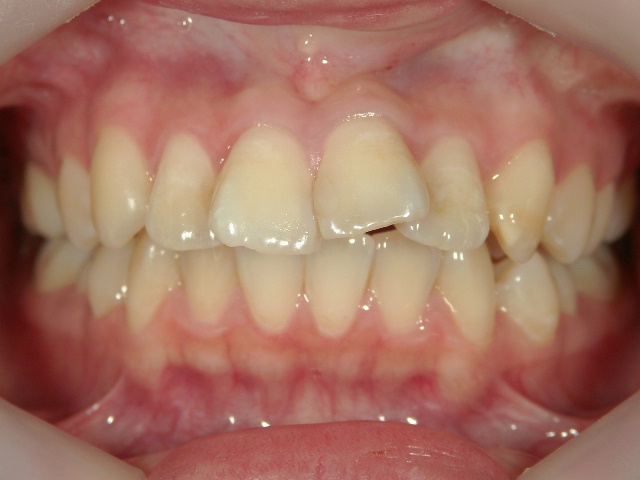

矯正歯科 治療前

no.6_8296_治療前_右.jpgno.6_8296_治療前_正面.jpgno.6_8296_治療前_左.jpg